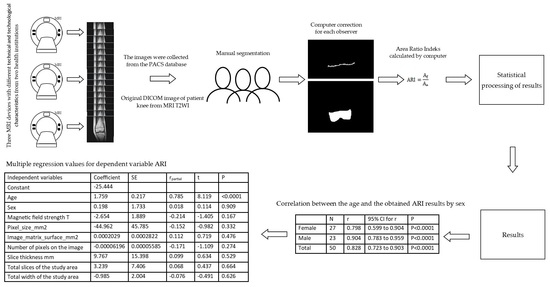

2. Materials and Methods

| N | r | 95% CI for r | p | |

|---|---|---|---|---|

| Female | 27 | 0.798 | 0.599 to 0.904 | p < 0.0001 |

| Male | 23 | 0.904 | 0.783 to 0.959 | p < 0.0001 |

| Total | 50 | 0.828 | 0.723 to 0.903 | p < 0.0001 |

| Independent Variables | Coefficient | SE | rpartial | t | p |

|---|---|---|---|---|---|

| Constant | −25.444 | ||||

| Age | 1.759 | 0.217 | 0.785 | 8.119 | <0.0001 |

| Sex | 0.198 | 1.733 | 0.018 | 0.114 | 0.909 |

| Magnetic field strength T | −2.654 | 1.889 | −0.214 | −1.405 | 0.167 |

| Pixel_size_mm2 | −44.962 | 45.785 | −0.152 | −0.982 | 0.332 |

| Image_matrix_surface_mm2 | 0.0002029 | 0.0002822 | 0.112 | 0.719 | 0.476 |

| Number of pixels on the image | −0.00006196 | 0.00005585 | −0.171 | −1.109 | 0.274 |

| Slice thickness mm | 9.767 | 15.398 | 0.099 | 0.634 | 0.529 |

| Total slices of the study area | 3.239 | 7.406 | 0.068 | 0.437 | 0.664 |

| Total width of the study area | −0.985 | 2.004 | −0.076 | −0.491 | 0.626 |